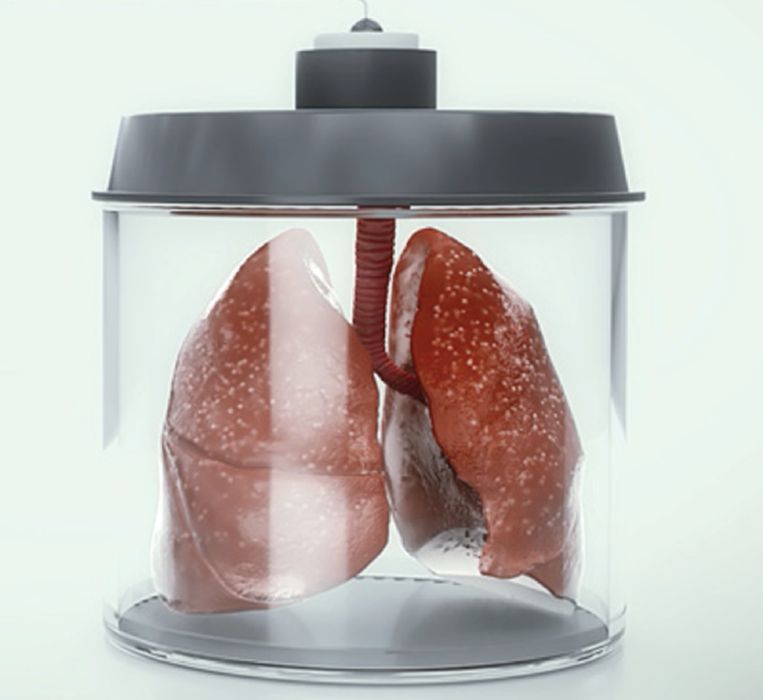

Frontier Bio’s New Bioprinting Technology Creates Functional Human Lung Tissue

Frontier Bio announced a key breakthrough in bioprinting: they’ve successfully 3D printed human lung tissue.